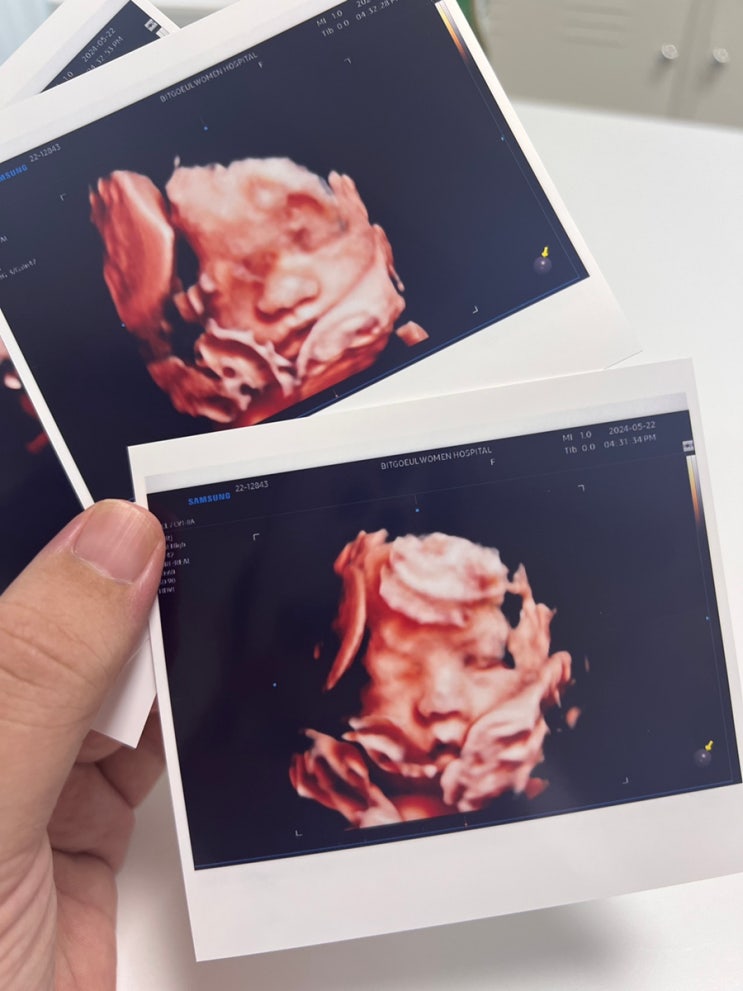

임신 19-20주 일상 안정기 시작 + 자궁수축

벌써 19주 일상..... 이라기엔 이걸쓰고 있는 오늘은 22주 0일이고요 ㅋㅋㅋㅋㅋㅋㅋㅋ 너어무 밀린 요즘 ...